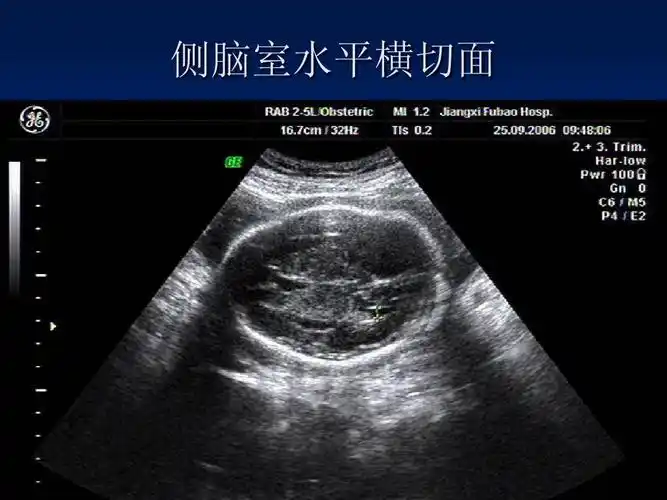

胎儿颅脑的超声所见

该切面显示上矢状窦,大脑镰,侧脑室,透明隔腔,丘脑,第三脑室,外侧裂